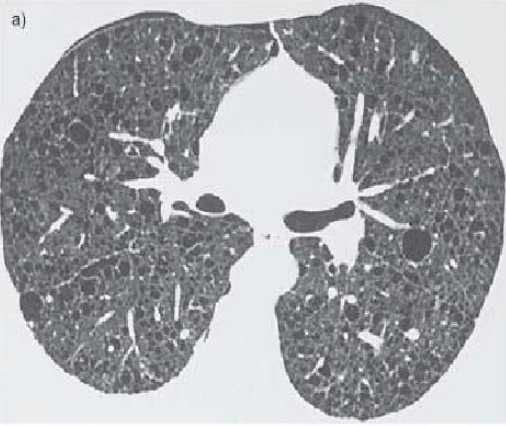

淋巴管肌瘤?。╨ymphangiomyomatosis,LAM)是一種比較罕見的疾病,幾乎所有的病例均發(fā)生于女性,以育齡期女性為主,平均年齡30~40歲。LAM主要累及肺臟,典型表現(xiàn)為彌漫性囊性改變,嚴(yán)重影響患者肺功能,而目前尚缺乏有效的治療方法。 2018年5月11日,國(guó)家衛(wèi)生健康委員會(huì)等5部門聯(lián)合制定了《第一批罕見病目錄》,淋巴管肌瘤病被收錄其中。 多發(fā)群體育齡期女性 常見癥狀自發(fā)性氣胸、乳糜胸、呼吸困難、咯血和胸痛等。 病因 LAM以不典型平滑肌細(xì)胞的過(guò)度增生為特征,病因不明。由于LAM發(fā)生于育齡期女性,推測(cè)其與雌激素有一定的關(guān)系。 臨床表現(xiàn) LAM常見呼吸系統(tǒng)癥狀包括自發(fā)性氣胸、乳糜胸、呼吸困難、咯血和胸痛等。通常起病隱匿,在臨床出現(xiàn)癥狀前可能已經(jīng)有活動(dòng)耐力差等表現(xiàn),隨疾病發(fā)展出現(xiàn)呼吸困難癥狀,并進(jìn)行性加重。氣胸和乳糜胸常為L(zhǎng)AM的首發(fā)癥狀,并可反復(fù)發(fā)生。在整個(gè)病程中,超過(guò)一半的患者會(huì)出現(xiàn)氣胸,乳糜胸見于20%~30%的患者。 LAM還可有肺外受累,例如,可有腹脹和腹痛等癥狀。腹部和盆腔CT檢查可發(fā)現(xiàn)淋巴結(jié)腫大、腹膜后淋巴管肌瘤、腎血管肌脂瘤。部分患者可出現(xiàn)乳糜腹水。 檢查 最具診斷價(jià)值的檢查為胸部高分辨CT(HRCT)。HRCT的典型改變?yōu)殡p肺彌漫性薄壁囊性改變。直徑在數(shù)毫米至數(shù)厘米。如果有氣胸、乳糜胸、淋巴結(jié)腫大及心包積液等,在CT上也會(huì)有相應(yīng)的表現(xiàn)。肺功能檢查在初期無(wú)明顯異常,以后出現(xiàn)阻塞或混合性通氣功能障礙,殘氣量增加,彌散功能下降。LAM的確診有賴于病理學(xué)檢查。獲取病理標(biāo)本的途徑有經(jīng)支氣管鏡肺活檢及手術(shù)肺活檢(小開胸或胸腔鏡下肺活檢)。 診斷 在臨床上,并非所有的患者均需要病理確診,有典型臨床綜合征和表現(xiàn)特征即可做出診斷。 臨床醫(yī)師在遇到女性患者,特別是育齡期女性,發(fā)生自發(fā)性氣胸或乳糜胸(兩者可以反復(fù)發(fā)生)時(shí),或者是年輕女性出現(xiàn)慢性進(jìn)展的呼吸困難或低氧血癥時(shí),會(huì)想到LAM的可能。特別是女性患者同時(shí)出現(xiàn)氣胸(或乳糜胸)與雙肺彌漫性囊性病變時(shí),高度懷疑LAM的可能。 治療 LAM細(xì)胞的細(xì)胞核雌激素受體和孕激素受體常為陽(yáng)性。理論上,可以針對(duì)雌激素進(jìn)行治療,但實(shí)際應(yīng)用并沒有足夠的證據(jù)。近年來(lái),一些新的研究為L(zhǎng)AM的治療帶來(lái)了新希望。其中較為矚目的是雷帕霉素和多西環(huán)素。目前美國(guó)已經(jīng)開始雷帕霉素治療LAM的臨床研究。多西環(huán)素也將進(jìn)入臨床試驗(yàn)??梢灶A(yù)見,隨著對(duì)LAM研究的深入,新的治療手段一定會(huì)在臨床應(yīng)用。病情嚴(yán)重的病例可以考慮肺移植治療。肺移植:在比較嚴(yán)重的LAM患者,肺移植是一項(xiàng)有效的治療手段。在我國(guó),肺移植手術(shù)的開展不如西方國(guó)家普遍,但也已有幾家醫(yī)院有LAM患者肺移植的經(jīng)驗(yàn)。在手術(shù)前請(qǐng)與呼吸科和肺移植專家共同討論手術(shù)的適應(yīng)證、手術(shù)方式、風(fēng)險(xiǎn)、移植后治療以及費(fèi)用等。肺移植需要有合適的供體,一般需要等待比較長(zhǎng)的時(shí)間。在其他治療方面,需要根據(jù)臨床情況進(jìn)行個(gè)體化的治療。 1.氣胸 治療上包括兩個(gè)方面,一方面使萎陷的肺重新復(fù)張,另一方面預(yù)防氣胸復(fù)發(fā)。 少量氣胸可觀察,讓它自行吸收。臥床休息和吸氧有助于氣胸的吸收。另外,如果有咳嗽癥狀,需要用鎮(zhèn)咳藥物。在觀察過(guò)程中,應(yīng)注意觀察癥狀變化,并復(fù)查胸片。 胸管引流是治療氣胸的有效方法,它通過(guò)一根管道將胸腔內(nèi)的氣體排出。胸管引流術(shù)在局麻下進(jìn)行,除了疼痛,常見的并發(fā)癥有胸膜反應(yīng)、出血和感染等。經(jīng)胸管排氣通過(guò)接單向閥、水封瓶或負(fù)壓吸引等多種方法進(jìn)行。大部分患者通過(guò)以上治療獲得好轉(zhuǎn)。在以上簡(jiǎn)單方法無(wú)效,或反復(fù)發(fā)生氣胸時(shí),需要采取一些復(fù)雜的治療方法,如胸膜粘連術(shù)和手術(shù)等。 LAM患者在第一次發(fā)生氣胸后可能會(huì)再次發(fā)生氣胸,在恢復(fù)后需要注意預(yù)防。主要的預(yù)防措施包括減少呼吸系統(tǒng)感染(感冒、咽炎和肺炎),避免舉重物,保持大便通暢,不要突然起立等。 2.乳糜胸和胸腔積液 首先,在飲食方面,禁食和胃腸外營(yíng)養(yǎng)可消除乳糜液的來(lái)源,有利于胸導(dǎo)管修復(fù)。高蛋白高熱量無(wú)脂飲食可以降低乳糜液流量。為了化驗(yàn)或減輕呼吸困難癥狀,醫(yī)生通過(guò)胸腔穿刺的方法抽取胸液。多數(shù)患者通過(guò)簡(jiǎn)單的治療胸液逐漸吸收。如果效果不好,也可考慮胸膜粘連和結(jié)扎胸導(dǎo)管(胸腔內(nèi)的淋巴引流導(dǎo)管)等治療手段。 3.血管肌脂瘤 血管肌脂瘤(AMLs)是一種主要發(fā)生在腎臟的良性腫瘤,腎臟外的血管肌脂瘤比較罕見,可見于肝臟、子宮、淋巴管和血管等部位。許多患者的AML并無(wú)癥狀,通過(guò)腹部超聲檢查和CT有助于診斷。不同患者AML增長(zhǎng)的速度是不一樣的。在治療方面,如果腫瘤小于4厘米而沒有癥狀,可通過(guò)CT或超聲隨訪了解其增長(zhǎng)速度;如果小于4厘米同時(shí)有后背疼痛、血尿等癥狀,應(yīng)該立即就診,需要考慮采取何種治療,如栓塞或手術(shù);對(duì)于大于5厘米的腫瘤,應(yīng)該考慮經(jīng)導(dǎo)管栓塞或手術(shù)切除。 4.骨質(zhì)疏松 骨質(zhì)疏松在LAM很常見,有一些治療,如孕激素、吸入皮質(zhì)激素、卵巢切除也可以增加骨質(zhì)疏松的風(fēng)險(xiǎn)。所以,LAM患者需要行骨質(zhì)疏松測(cè)定,如果出現(xiàn)骨質(zhì)疏松應(yīng)給予相應(yīng)的治療,如:補(bǔ)充鈣、維生素D和雙膦酸鹽等。生活中的一些細(xì)節(jié)有助于改善骨質(zhì)疏松。如戒煙、避免過(guò)量飲酒。少喝咖啡和碳酸飲料,注意營(yíng)養(yǎng)平衡,補(bǔ)充牛奶或豆?jié){。增加含鈣多的食品,如:深綠色蔬菜、蝦、等。運(yùn)動(dòng)起來(lái),比較簡(jiǎn)單的方法是跑步或走路,如:每天30分鐘運(yùn)動(dòng)。運(yùn)動(dòng)量和方式應(yīng)根據(jù)患者身體狀況而定,不要做超出自己能力的運(yùn)動(dòng)。在CT影像上以雙側(cè)彌漫性薄壁囊腫,無(wú)區(qū)域分布傾向(圖1和圖2)。LAM 可僅累及肺部,但也可為全身性疾病。肺LAM表現(xiàn)也可合并結(jié)節(jié)性硬化。當(dāng)LAM為全身性或合并結(jié)節(jié)性硬化時(shí)可出現(xiàn)其他表現(xiàn),最常見為腎血管平滑肌脂肪瘤(圖11-1)。腹盆部由于淋巴管阻塞(淋巴管平滑肌瘤)可見淋巴結(jié)腫大和擴(kuò)張囊性腫塊。淋巴管阻塞也可導(dǎo)致乳糜性胸腔積液(圖3)。20%發(fā)生自發(fā)性氣胸。 重點(diǎn) LAM為一種肺部進(jìn)行性疾病,預(yù)后較差,典型地累及育齡婦女。在適當(dāng)?shù)呐R床資料下CT表現(xiàn)可以診斷。 相關(guān)臨床知識(shí) LAM幾乎只限育齡婦女患病。其典型表現(xiàn)為進(jìn)行性呼吸短促,但如果自發(fā)性氣胸為首發(fā)時(shí)也可出現(xiàn)急性氣短。 鑒別診斷 主要鑒別考慮為肺朗格漢斯組織細(xì)胞增生癥(PLCH)。不過(guò),LAM不伴有結(jié)節(jié),而表現(xiàn)典型地出現(xiàn)在PLCH中。此外,更重要的診斷性觀察是在PLCH患者其肺底不受累,而LAM則表現(xiàn)為肺彌漫性囊性改變。肺部其他囊性疾病如淋巴細(xì)胞型間質(zhì)性肺炎和Birt-Hogg-Dubé綜合征極為少見且有其他臨床表現(xiàn),應(yīng)該可以鑒別。肺氣腫可 偶然誤認(rèn)為肺囊性疾病。不過(guò),囊腔內(nèi)無(wú)囊壁而且囊狀影中有小葉中心結(jié)構(gòu)(小動(dòng)脈),應(yīng)該可以鑒別。 教學(xué)要點(diǎn) 在適當(dāng)?shù)呐R床情況下,呈雙側(cè)彌漫性薄壁囊腫的CT表現(xiàn)可診斷為L(zhǎng)AM。辨別出LAM的肺部表現(xiàn)時(shí),應(yīng)注意腎臟尋找合并血管平滑肌脂肪瘤。 A.結(jié)節(jié)性硬化癥和LAM女性患者的胸部 CT。主動(dòng)脈弓水平軸位圖像顯示雙側(cè)多發(fā)薄壁囊腫。 B.胸部CT軸位肺底部圖像顯示彌漫性薄壁囊腫且肺底部無(wú)例外。 C.腹部CT增強(qiáng)掃描顯示雙側(cè)腎臟含脂肪腫塊符合血管平滑肌脂肪瘤(白箭) 女性LAM患者的胸部CT。主動(dòng)脈弓下方水平軸位圖像(A)和肺底軸位圖像(B)顯示雙側(cè)彌漫性薄壁囊腫 女性LAM患者胸部CT冠狀位重建顯示雙側(cè)彌漫性薄壁囊腫。同時(shí)顯示由于胸腔積液使左側(cè)肋膈角變鈍(黑箭),后來(lái)證實(shí)為乳糜液。

流行病學(xué) LAM是一種肺部的罕見病,主要患者為育齡期女性,每1百萬(wàn)女性中就有2~5位女性患有此病。LAM是一種罕見的疾病,它可以散發(fā)或與遺傳病結(jié)節(jié)性硬化癥(TSC)有關(guān)。成年女性散發(fā)的LAM發(fā)病率大約1400,000;成年女性TSC患者LAM的發(fā)病率大約是30-40%。男性和兒童TSC患者中幾乎沒有LAM的報(bào)道。 病理學(xué) 該疾病主要表現(xiàn)為異常生長(zhǎng)的平滑肌細(xì)胞侵入肺部組織(包括氣管、血管和淋巴管腔),引起肺部損傷,進(jìn)而導(dǎo)致氣流阻塞及供氧障礙。 臨床表現(xiàn) 1、逐漸加重的呼吸困難和復(fù)發(fā)性氣胸、乳糜胸和偶爾咯血。 2、淋巴管平滑肌瘤(肺外淋巴結(jié)腫大和中軸淋巴管囊性腫塊)可導(dǎo)致腹腔和盆腔淋巴管阻塞。 3、有的患者出現(xiàn)腎血管肌脂瘤、腦膜瘤發(fā)病率升高。 診斷 診斷需要組織活檢(通常從肺,偶爾從淋巴結(jié)或淋巴管平滑肌瘤)和/或結(jié)合病史與胸部HRCT 影像學(xué)特點(diǎn) HRCT是包括LAM在內(nèi)的彌漫性實(shí)質(zhì)性肺疾病的診斷、評(píng)估、隨訪的推薦影像學(xué)檢查方法。 肺部囊性病變是LAM病變的主要特征。其外形、大小、輪廓變化很大,多數(shù)直徑在2-5mm,偶爾可達(dá)到30mm。囊通常是圓形,均勻分布在全肺,肺實(shí)質(zhì)正常。大多數(shù)囊壁厚度